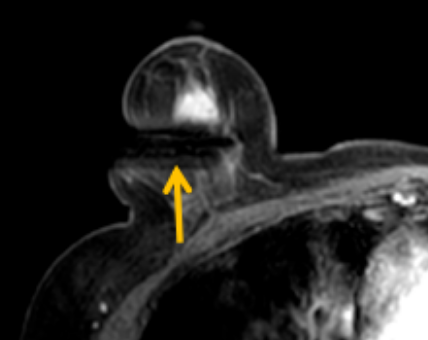

陳寶瑩評估圖像后發(fā)現(xiàn)病變?yōu)閮H僅在磁共振增強(qiáng)時(shí)顯示,為非腫塊樣病變,比較散,必須取得足夠多的組織才能確保病理檢查的準(zhǔn)確性,常用的核芯針活檢獲取的組織較少,因此最終確定了磁共振引導(dǎo)下行真空輔助抽吸旋切活檢。取得患者及家屬認(rèn)可后,陳寶瑩帶領(lǐng)團(tuán)隊(duì)開始進(jìn)行術(shù)前準(zhǔn)備。

針對患者乳房小固定難度大這一問題,陳寶瑩通過巧妙體位和固定器的調(diào)整,順利固定好乳房。經(jīng)過磁共振多模態(tài)掃描,陳寶瑩找出病變活性成分相對集中區(qū)域,精準(zhǔn)確定穿刺路徑,置入引導(dǎo)針、旋切針,到位后多角度旋切取出足量組織,拔除旋切針后即時(shí)行磁共振掃描,精準(zhǔn)取得組織且術(shù)區(qū)出血很少,遂加壓包扎,整個過程非常順利,旋切活檢后患者回家休息。兩天后隨訪,李女士沒有任何不適,五天后皮膚上幾毫米的小切口已經(jīng)愈合。最終病理結(jié)果證實(shí)為乳腺導(dǎo)管原位癌,為早期乳腺癌,為患者后續(xù)針對性治療奠定了基礎(chǔ)。